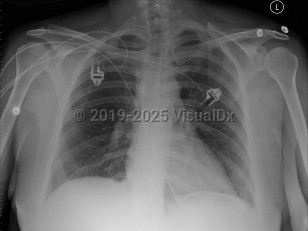

Imaging Studies image of Pulmonary embolism - imageId=2956045. Click to open in gallery.  caption: 'Frontal chest x-ray with no definite acute disease, most common finding on chest x-ray with pulmonary emboli.'

Frontal chest x-ray with no definite acute disease, most common finding on chest x-ray with pulmonary emboli.